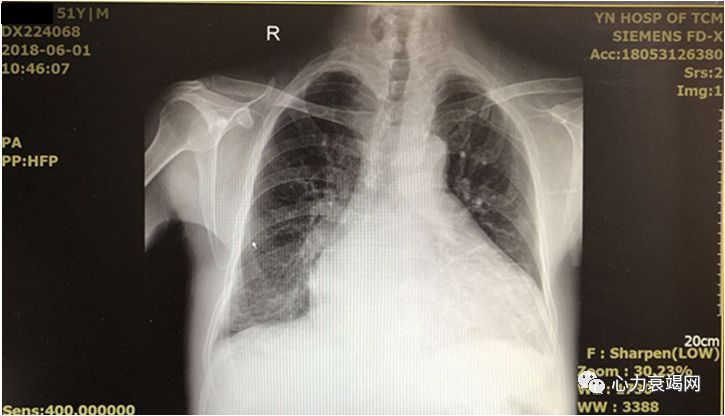

全心扩大

二尖瓣、三尖瓣中-大量反流

左心室收缩、舒张功能减低

EF:10%